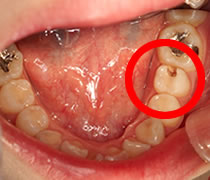

抜髄の症例(24歳女性の場合)

初診時

「左下の奥歯が痛いため、根管治療の専門医に診て欲しい」とのことでした。

診断結果と治療方針の決定

虫歯がかなり深く進行して、神経近くに達し、歯髄炎を起こしている状態でした。

抜髄と根管充填を行った後に適切な歯冠修復処置を行ないます。

根管治療1日目

局所麻酔をした後に虫歯を取り除きます。奥歯との隙間をレジンで補強して隔壁を作成、破折と唾液の混入を防ぎます。ラバーダムを装着します。

次に、炎症を起こした歯髄を取り除き、根管の内部をお掃除して、細菌を除去します。根管内のお掃除が終わったら、根管内を薬品で洗浄し、根管内を殺菌します。

- 左下の奥歯が虫歯のため、

穴が空いていました。

- 虫歯を取り除くと

神経(歯髄)の一部が

露出して出血しています。

- 痛みが出てしまった神経は

取り除く。

炎症を起こして充血した神経。